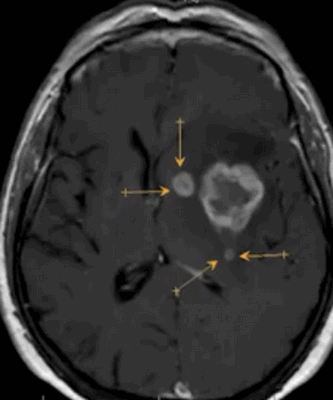

Глиобластома на МРТ головного мозга без контраста

Метастазы в головном мозге на постконтрастном изображении (указаны стрелками)

До- и постконтрастное изображение злокачественной опухоли головного мозга

Опухоль головного мозга на МРТ с отсевами (указаны стрелками)